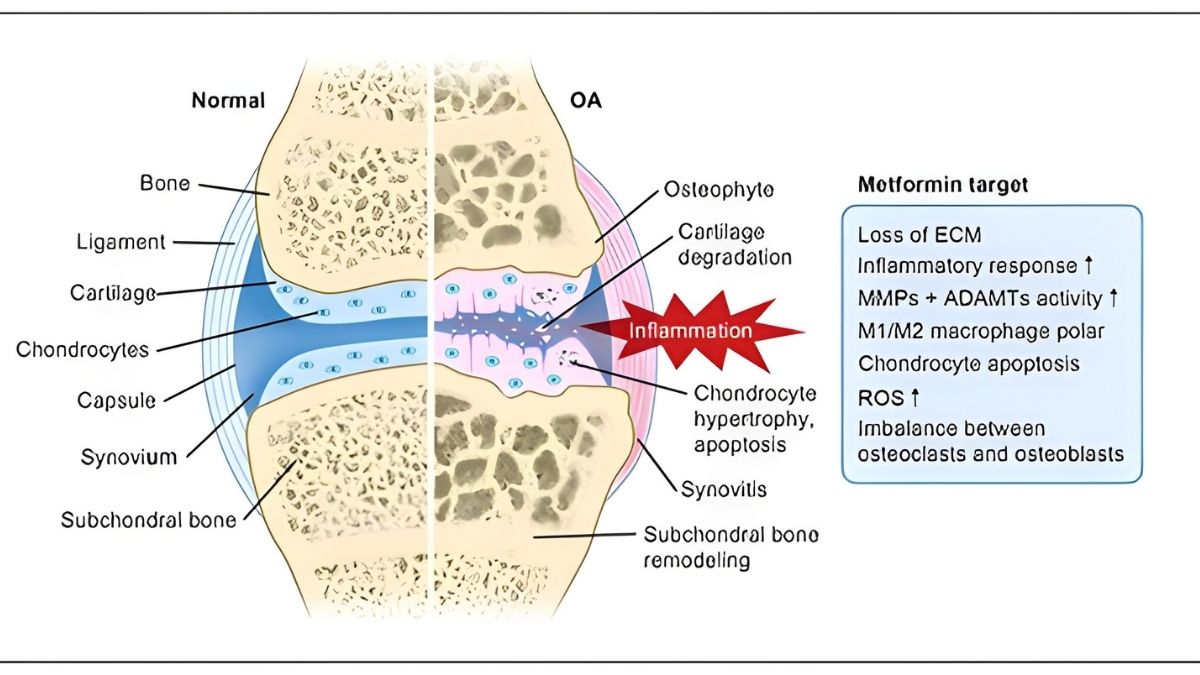

AGEs bind to receptors called RAGE. This triggers an inflammatory explosion. Your cells release TNF-α and IL-1β. These signals tell your body to break down cartilage. Enzymes called MMPs (matrix metalloproteinases) start destroying the cushioning in your joints. At the same time, Reactive Oxygen Species damage your cell DNA and proteins.

- MMPs break down cartilage

- ROS damage cell DNA

In arthritic joints, adiponectin increases MMP-1 and MMP-3 production. These enzymes chew up cartilage. Research shows adiponectin correlates with aggrecan degradation—that’s the main cushioning protein in your joints breaking apart. Higher adiponectin doesn’t protect you. It makes things worse.

Insulin resistance doesn’t just affect diabetes. It affects your joints too. Type 2 diabetes causes damage through oxidative stress and chronic inflammation.

Studies on diabetic mice showed increased cartilage damage and synovial inflammation after just 10 weeks. Human patients with diabetes report worse pain on WOMAC scores—a standard arthritis pain measurement.

Metformin’s Emerging Role

Metformin is an old diabetes drug showing new promise for OA. A network meta-analysis ranked it highest for pain relief among medications studied. It activates AMPK pathways and reduces inflammation.

The safety profile looks good in OA patients with or without diabetes. Research is ongoing. Talk to your doctor about whether metformin makes sense for you.